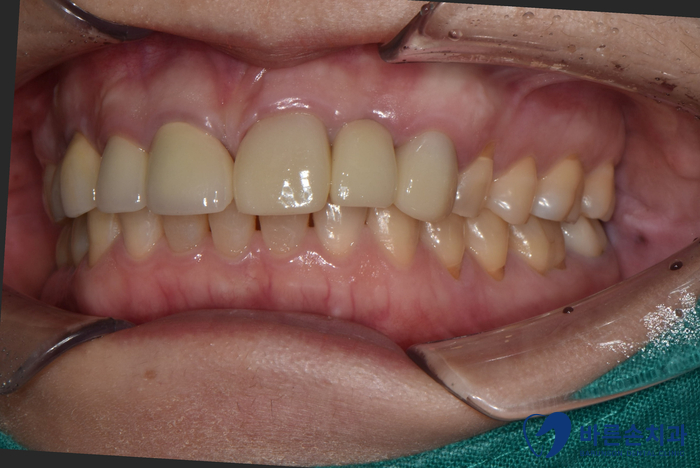

크라운과 임플란트 보철이 완성된 모습입니다!

임플란트 보철물도 주변 자연치아와 잘 조화되어

큰 이질감이 없어요!!

다행히 기존 내 치아를 살리면서 치료를 마칠 수 있었어요.

너무 다행입니다.^^